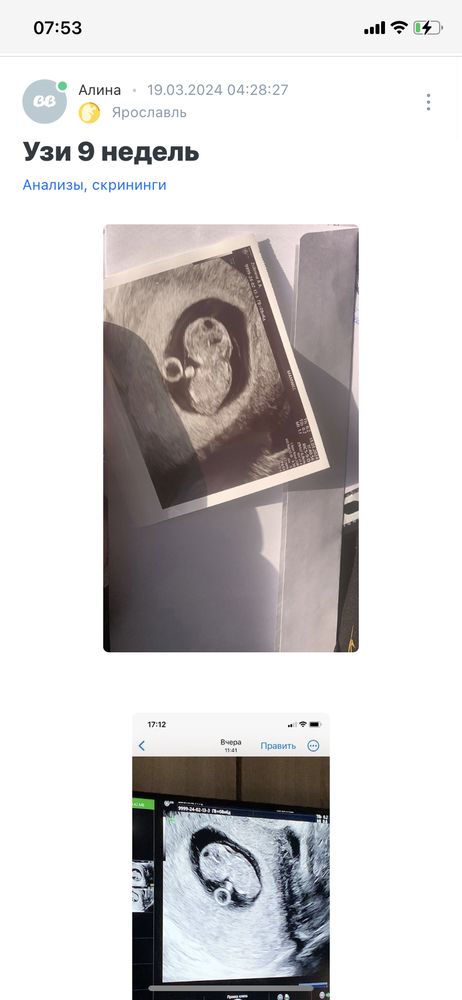

Девочки, доброе утро.. Приложу описание своей ситуации по узи в 9 -то неделек (первые пять фото). Ходила на узи в 9,5 недель (шестое фото) Всё таки есть расширение воротникового пространства? Хожу в платную клинику с самого начала беременности. Попросила её измерить все таки, она померила, но там, где маленькое воротниковое пространство и сказала 1,5, но можно было замерить в другом месте, где оно больше. Вроде в конце она померила большой замер и ничего не сказала мне, а я обратила на это внимание 😢 Я её спросила несколько раз, она сказала, что все хорошо, но мне кажется, что она меня так просто успокаивает..